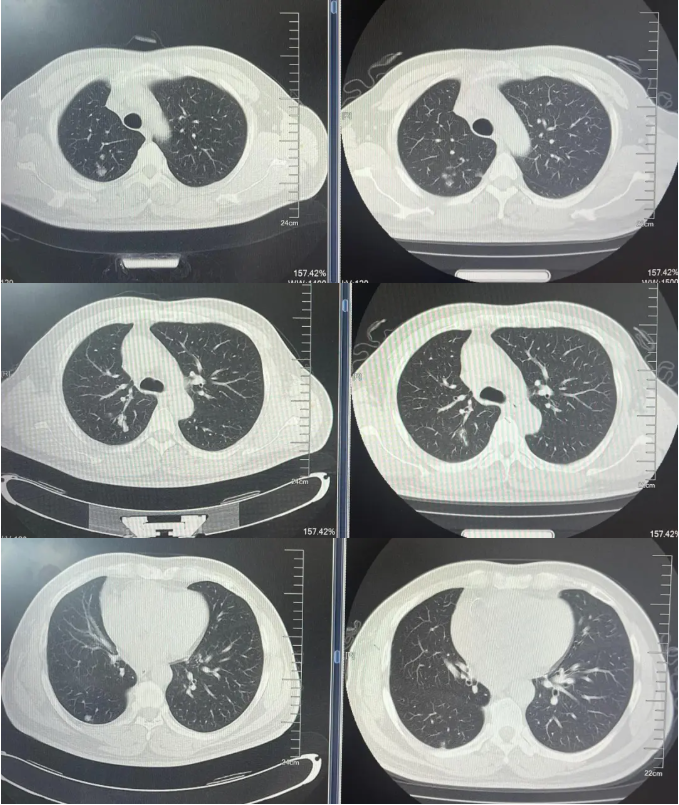

病例1:患者男,68岁。2024年6月以“胸闷气短1个月”为主诉于当地医院检查治疗。查CT提示左肺下叶肿物,纵隔、双肺门多发肿大淋巴结,左侧胸腔积液,左侧胸膜增厚。于当地医院行胸水穿刺引流查癌细胞提示肺腺癌。临床分期:cT2aN3M1a IVA期。患者于当地医院行血液基因检测未见敏感突变,使用AP方案化疗后病情进展。2025-1入我院后行肺穿刺活检,病例提示腺癌。行基因检测提示:ERBB2突变(丰度3.5%)。行德曲妥珠单抗(T-DXd)治疗至今。最佳疗效PR,目前持续有效中,PFS已超过7个月。患者使用德曲妥珠单抗期间出现II级恶心呕吐,经对症治疗可缓解。

德曲妥珠单抗治疗4周期(2025.5)疗效对比

德曲妥珠单抗治疗6周期(2025.7)疗效对比